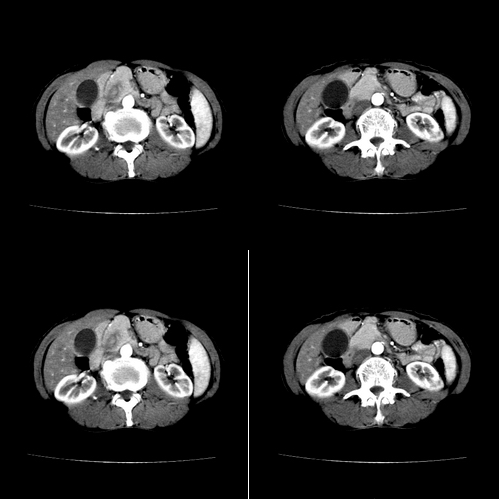

患者 女 60岁,曾多年胆结石及胆管结石,今行ct复查,非常经典.现上传,请讨论.

典型的胆总管铸型结石。

支持胆总管结石。胆囊增大受压,肝内胆管及胰腺管无明显扩张。很有意思的病例,能有冠、矢状重建图像观察就更好了。

相当漂亮的“总胆管(铸型)结石”。多谢楼主!

胆总管内多层同心圆样结石,确属精典,谢谢卜一老师!

肝内胆管扩张形态也支持胆总管结石的表现